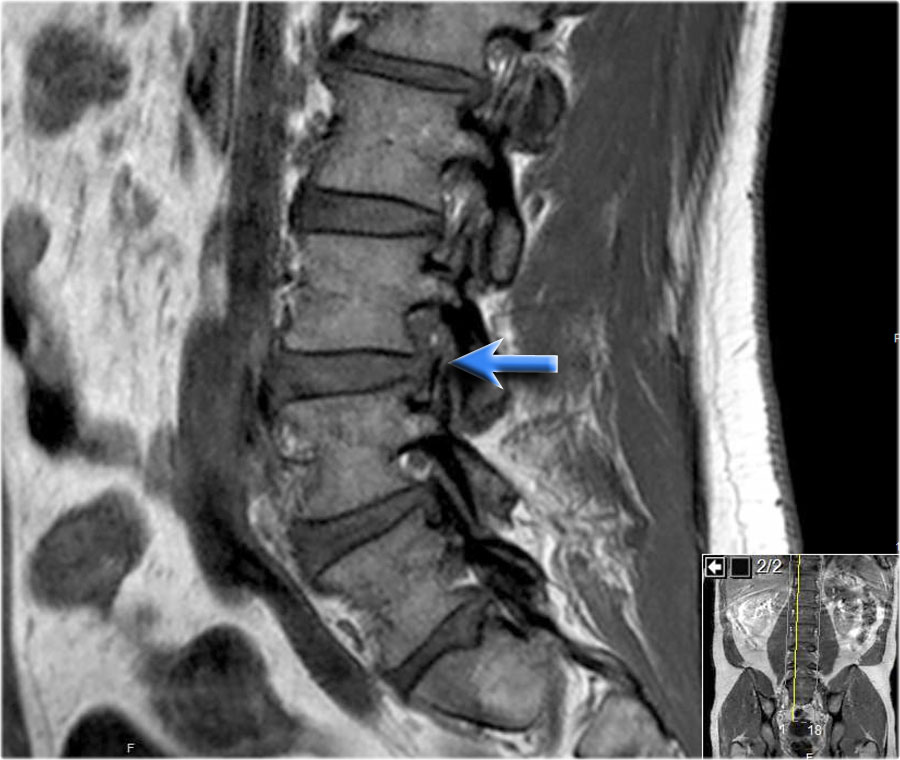

Trước tiên hãy quan sát các hình ảnh.

Nhấp để phóng to.

Sau đó tiếp tục đọc.

Các dấu hiệu bao gồm:

- Thoát vị đĩa đệm L3L4.

- Di trú lên phía trên.

- Chèn ép rễ thần kinh L3 trong lỗ liên hợp.

Cường độ tín hiệu của thoát vị đĩa đệm trên chuỗi xung T1W thường ở mức trung gian, trong khi trên chuỗi xung T2W có thể tăng tín hiệu trong trường hợp nhân nhầy thoát vị mới hoặc giảm tín hiệu trong trường hợp thoát vị cũ hơn.

Hình ảnh thoát vị tăng tín hiệu (mũi tên vàng trên ảnh cắt ngang) trượt qua vết rách vòng sợi và chèn ép rễ thần kinh L5 bên trái (mũi tên xanh dương).